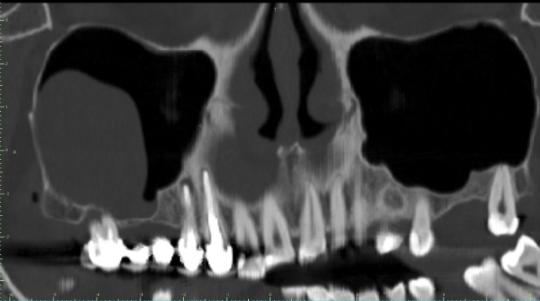

Material y método: la población estudiada son 24 pacientes, 16 de sexo femenino (66,6%), y 8 de sexo masculino (33,33%), con edades comprendidas entre los 12 y 15 años, que presentaron un valor del ángulo ANB de clase II (ángulo formado por el punto A – punto Na – punto B). Se utilizaron las telerradiografías laterales de cráneo iniciales y finales del mencionado grupo, habiéndose creado un método específico de 26 medidas para realizar la investigación.

Resultados: en los resultados obtenidos de la muestra se ha observado un claro aumento de los valores del crecimiento mandibular, tanto verticales como horizontales, como los valores que evalúan la posición sagital horizontal de los dientes inferiores del grupo estudiado.